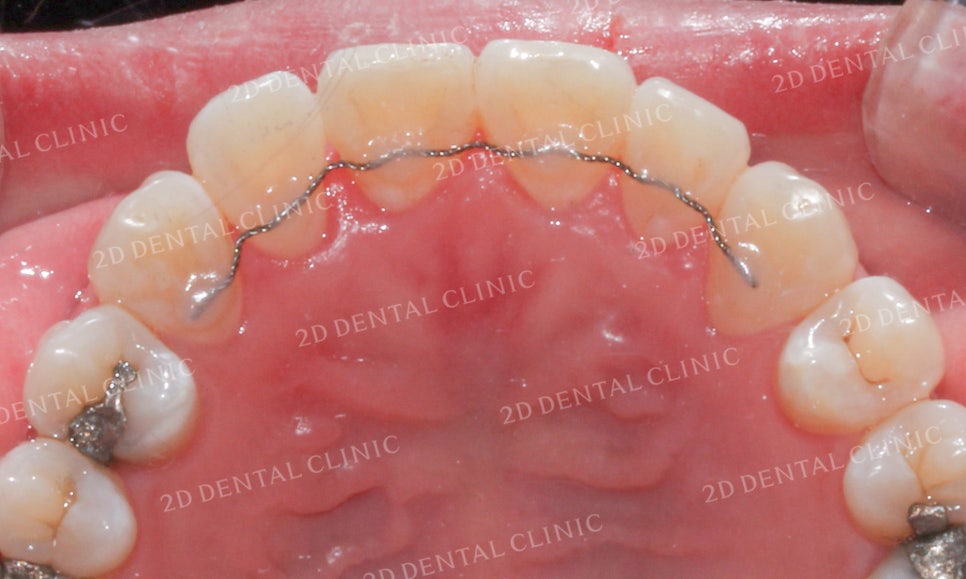

<Before> <After>

![[앞니교정]부정교합교정, 부분교정으로 완성하기! by.투디치과(2D치과) 관련 이미지 15](https://pub-9f2bb3498faf4d1d8714b41df24753e3.r2.dev/content/clinics/archive/grb36g4zmx/naver_blog/dental2d/assets/by_hash/104559ab18a1a5de0176f9bdcc32a8b124df7f3b04f40bc58cf2442e20735b73.jpg)

![[앞니교정]부정교합교정, 부분교정으로 완성하기! by.투디치과(2D치과) 관련 이미지 16](https://pub-9f2bb3498faf4d1d8714b41df24753e3.r2.dev/content/clinics/archive/grb36g4zmx/naver_blog/dental2d/assets/by_hash/b12d35e0eab682b41eede6e5935ff00f15597a19daf5071d7190930e86c5f941.jpg)

설측에서 본 상악 역시

안쪽으로 강하게 꺾여있던 측절치가

정상 각도를 되찾은 모습입니다!